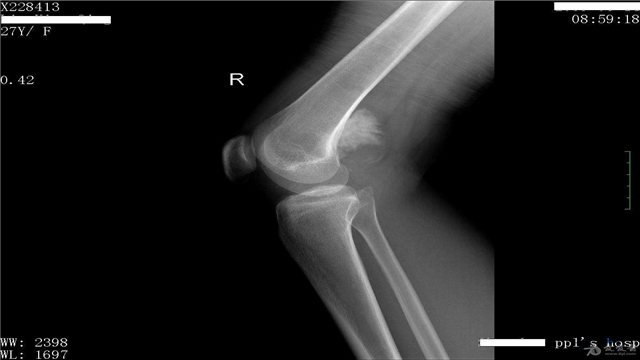

骨肉瘤,是一种常见于10岁到30岁的青少年的骨恶性肿瘤(有说24岁以上就是中年,这里大家就别追究这点了,大伙都是年轻人。)没错是骨头,也许有人会说,骨头不是没有活细胞么?大家不要忘了,在这一阶段的人群,骨骼是处于发育期的,不然你拿什么来长高啊。

骨肉瘤是由骨间质细胞发展而来,在软骨阶段直接或间接的形成了肿瘤骨样组织和骨组织,常发生于下肢,多源于骨内。